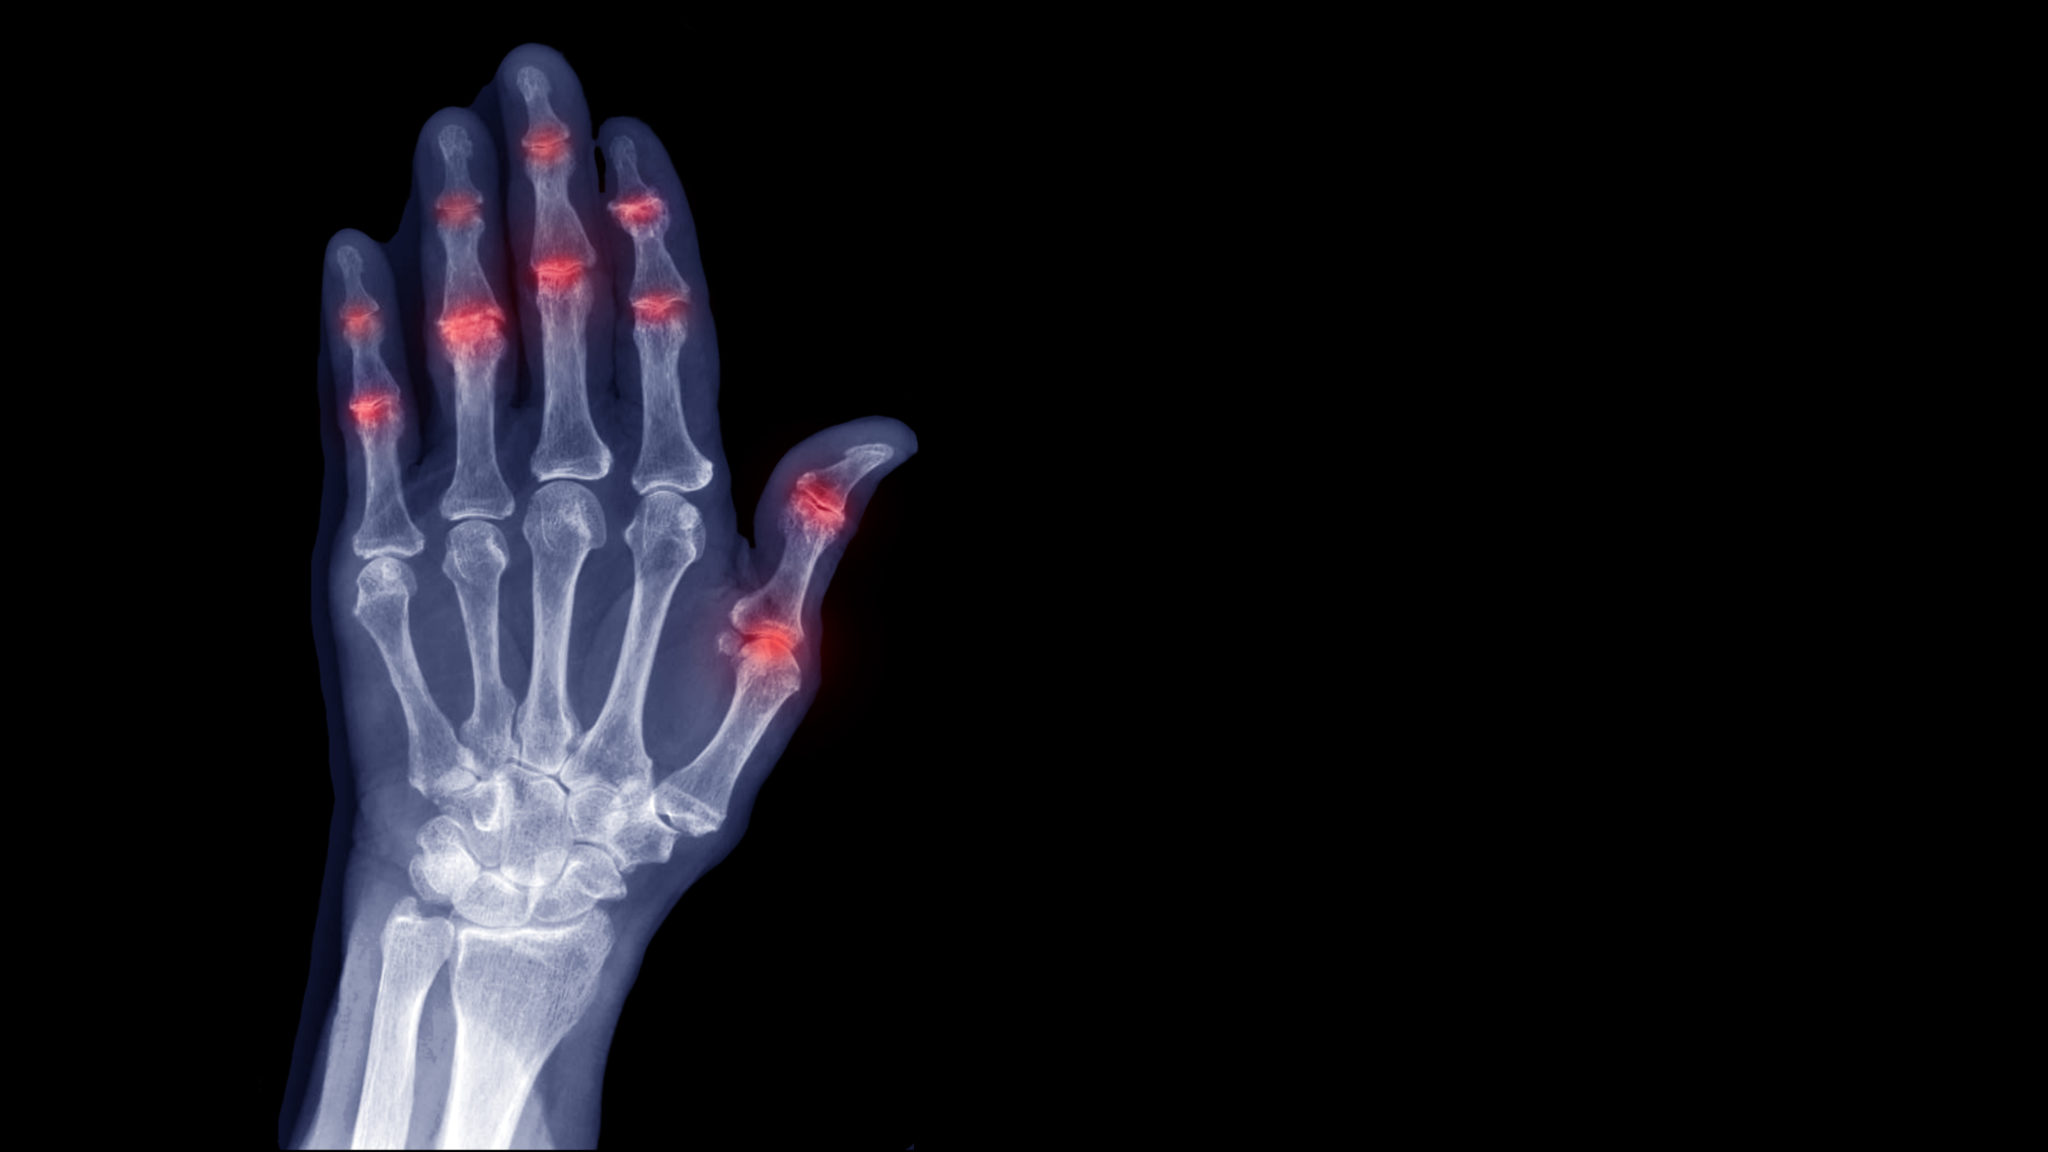

Apr 9, 2025 · When you have rheumatoid arthritis, your immune system sends antibodies to the synovium and causes inflammation. This causes pain and joint damage, especially in small joints in the fingers and …